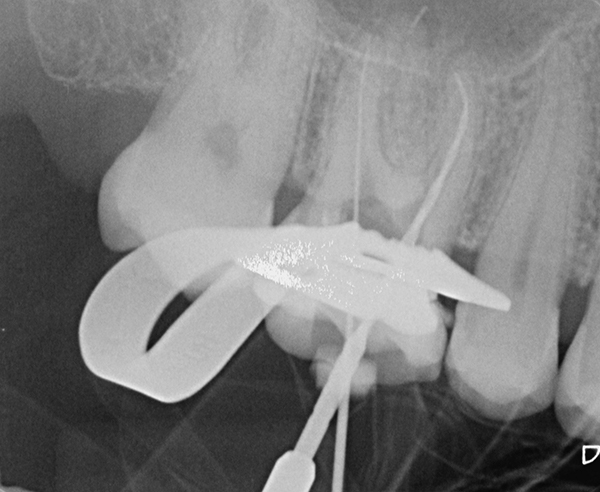

Fall 2: Revision und Entfernung einer abgebrochenen Feile + starke Krümmung in der mesialen Wurzel

Die Patientin wurde zu uns überwiesen mit der Bitte um Revision. Erst die vorab angefertigte DVT ließ einen frakturierten Fremdkörper in der distalen Wurzel erahnen. Diese Vermutung bestätigte sich auch nach der Entfernung des alten Wurzelfüllmaterials. Mithilfe von Ultraschall konnte die Feile entfernt werden und der Kanal bis nach apikal aufbereitet werden.